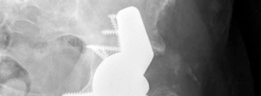

Diagnosis : Dislocated left total hip arthroplasty secondary to septic loosening and suspected corrosion and trunnionosis of the femoral stem (Figs. 19.23 and 19.24).

Reconstruction techniques : A hemispherical socket was placed; however, in the presence of posterior wall deficiency, a buttress augment was utilized to support the socket. The cup was fixed with multiple screws, and demineralized bone matrix was placed behind the acetabulum. The augment and the acetabular components were adjoined with the use of cement (Figs. 19.25 and 19.26).

(Figs. 19.25 and 19.26)